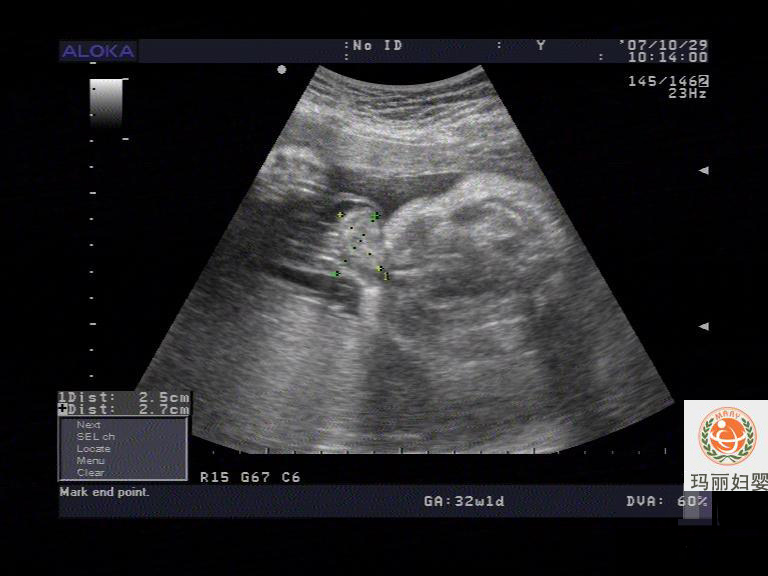

胎儿腹部脐带起始部膨大范围2.5×2.7CM,内见肠管样偏强回声团;

3、胎儿脐膨出